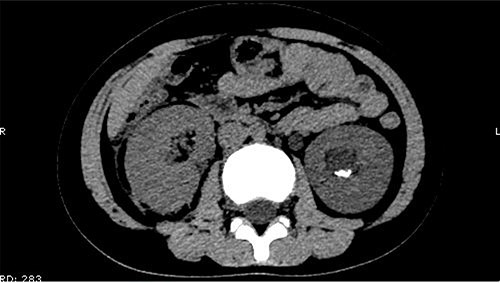

The patient was confined to bed, fasted and prescribed a daily intravenous infusion of cefazolin sodium pentahydrate, 2.0 g for 10 days. CT showed some irregular high-density shadows were present in the left renal pelvis (Fig. 1), and a small strip of high-density shadow was apparent in the bladder cavity (Fig. 2). Blood tests showed no abnormality in serum calcium concentration. Cefazolin sodium pentahydrate was discontinued immediately.

A small strip of high-density shadow was present in the bladder cavity.